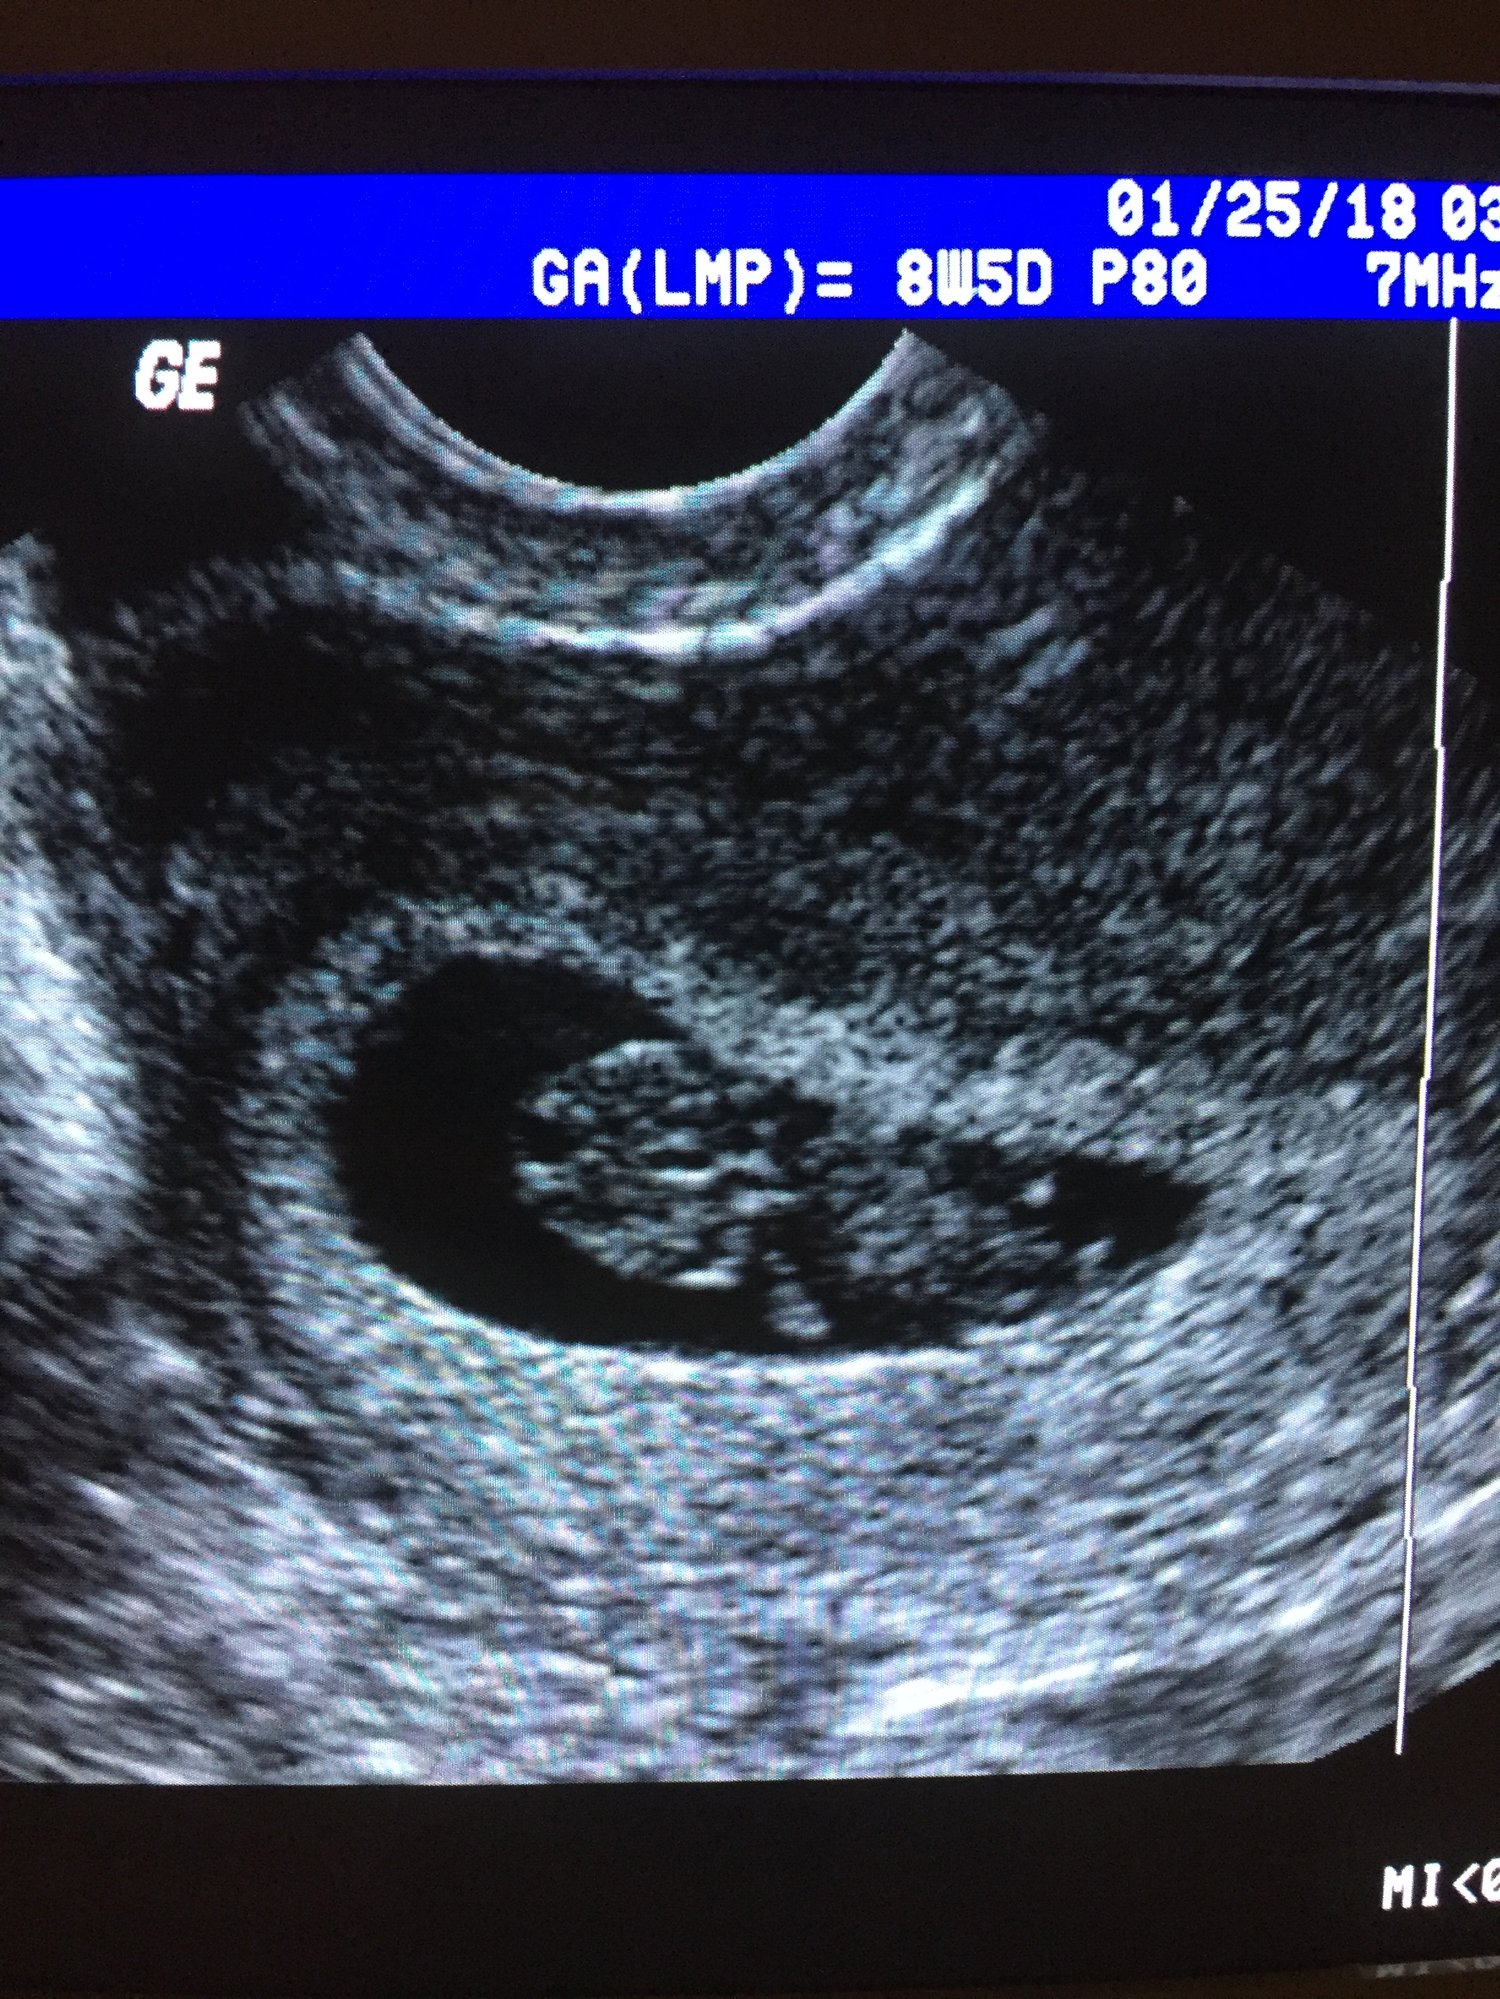

7+2 today, EDD 9/10/18

I've had two US so far, at 5 and 7 weeks. At the last US at 7 weeks we saw the heartbeat, measuring at 120 BPM, but my RE said size-wise its only measuring at 6+2. She said that it's common after FET to be behind in growth and doesn't seem concerned, but of course I can't help but be worried. Any one else experience this? I'm trying not to stress, but after so many years of failure I'm just waiting for the other shoe to drop.

Next US scheduled for 1/31 which will be 8+2

@sarzee2 It's my understanding that frozen transfers can take a few days to "wake up" after being frozen sometimes. I hope your babe is just a little lazy ;)